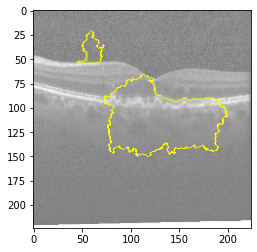

Original Image

Explanation B

Explanation C

Explanation D

GradCAM

Original Image

Explanation B

Explanation C

Explanation D

GradCAM

V MODEL EXPLANATION WITH XAI

Fig 6, 7, 8 and 9 depicts the visualization of correct predictions by our proposed CNN model where fig 6 is class CNV, fig 8 is class DME, fig 7 is DRUSEN and finally, fig 9 is NORMAL. Here the first photo in every class is the original image. The LIME map of our suggested model’s prediction is shown in image B whereas in image C the positive region is highlighted in specific sections on the original image. For Image D we have increased the number of features from 5 to 10 thus more regions have been predicted as the positive region which is highlighted in green. After increasing the features from 5 to 10, some of the regions are predicted wrongly. The red regions represent the output of incorrect prediction. The following image represents the Grad-CAM heatmap highlighting the regions with our model’s prediction.